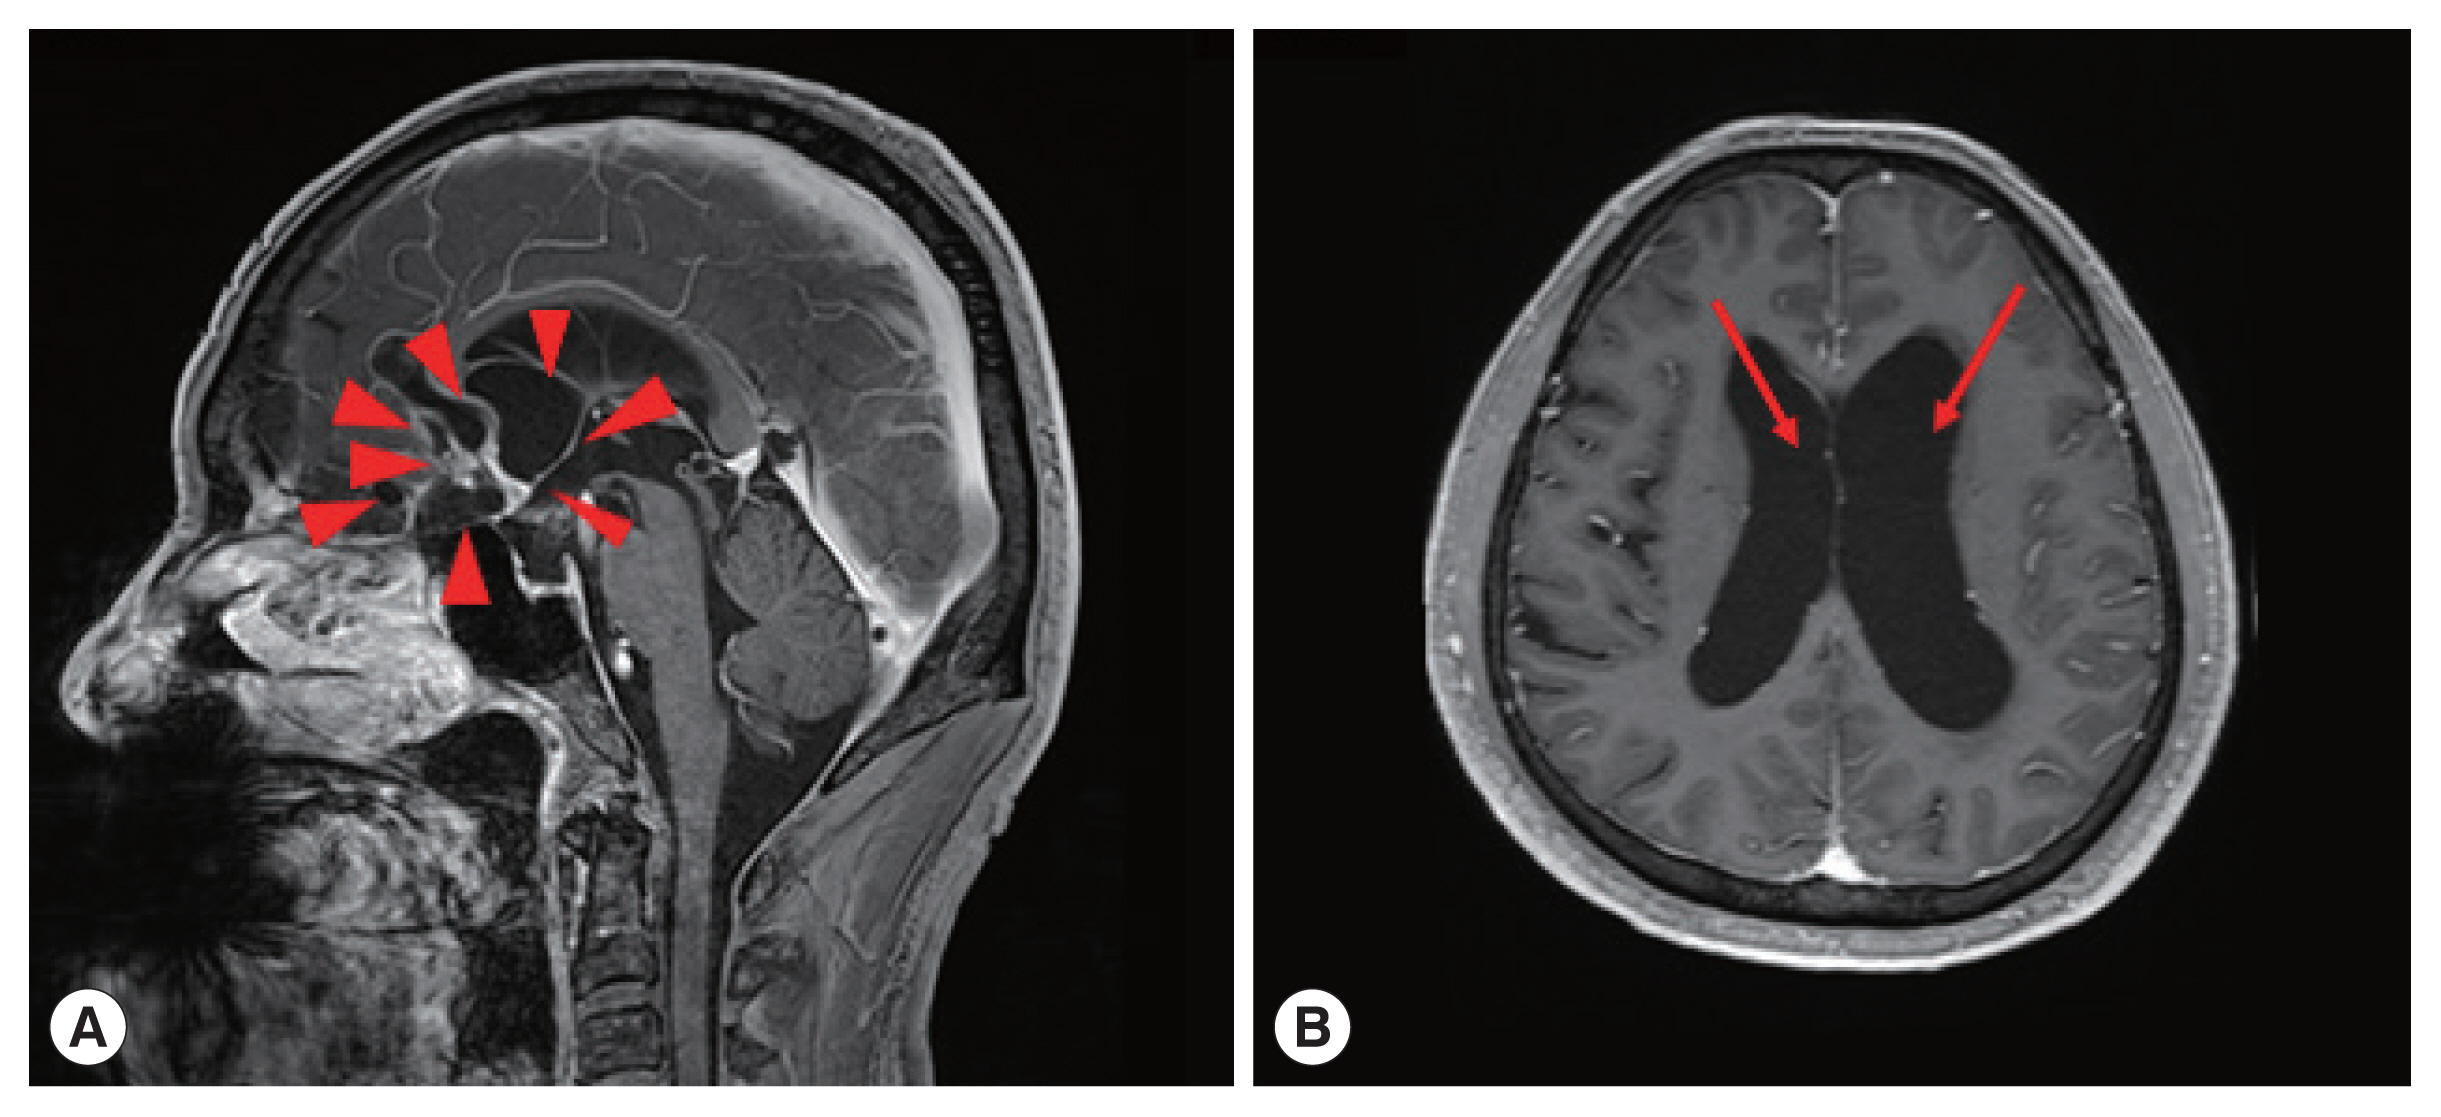

One of the patients was a 66 year old male with no previous medical history, who was admitted with symptoms of headache, vertigo, and gait disturbance. He had a history of working in Libya 35 years ago, and a history of travel to Vietnam (4 years ago) and China (1 year ago). CSF findings showed eosinophilic pleocytosis (CSF white blood cell count 29/μl, eosinophil percentage 18%), with elevated protein levels (89.3 mg/dl) and normal glucose levels (56 mg/dl). Brain MRI showed multiple cystic lesions with focal wall enhancement at both frontal base and subcallosal areas, with ventriculomegaly of both lateral ventricles and the 3rd ventricle (Fig. 1). Multiple calcific nodules in soft tissue were seen on chest imaging (Fig. 2). Based on these findings, immunodiagnostic testing for parasite infections were performed on the patient’s blood and CSF. Both serum and CSF cysticercus antibodies were positive, and the patient was diagnosed with neurocysticercosis. Albendazole was administered for 4 weeks, in combination with dexamethasone. Afterwards, his symptoms of headache improved, but his limping gait worsened, leading to a second course of therapy with albendazole, praziquantel, and steroids 3 months after the initial treatment. The patient showed slight improvement in symptoms before he was transferred to another hospital, and follow-up was lost.

Fig. 1

Brain magnetic resonance imaging (MRI) of a patient diagnosed with neurocysticercosis. (A) Multiple cystic lesions with focal wall enhancement are seen at both frontal base and subcallosal areas, suggestive of parasitic cysts (red arrowheads). (B) Ventriculomegaly of both lateral ventricles (red arrows) can be seen.

Fig. 1 Brain magnetic resonance imaging (MRI) of a patient diagnosed with neurocysticercosis. (A) Multiple cystic lesions with focal wall enhancement are seen at both frontal base and subcallosal areas, suggestive of parasitic cysts (red arrowheads). (B) Ventriculomegaly of both lateral ventricles (red arrows) can be seen.